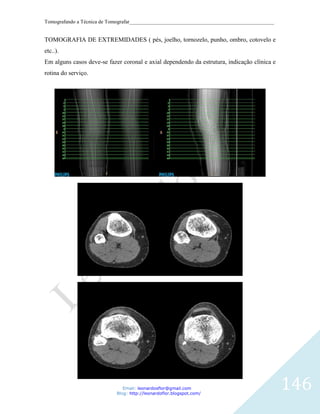

Tomografando a Técnica de Tomografar_______________________________________________________

ESPAÇO CERVICAL ANTERIOR: estende-se desde o osso hióide até a clavícula e está

preenchido por gordura. A fáscia visceral o separa do espaço visceral medialmente; a

camada superficial da fáscia cervical profunda limita o espaço ântero-lateralmente e a

bainha carotídea o limita posteriormente. O espaço submandibular está situado

superiormente, sem separação por planos fasciais.

Lesões: lipoma, cisto branquial, abscesso e linfangioma

TÉCNICA DE EXAME

O paciente é deitado na mesa de exames e lentamente será levado para o interior do gantry,

onde serão feitas as imagens da região cervical. É muito importante permanecer imóvel e

seguir as instruções do profissional que realizará o exame. O tempo de exame é variável,

podendo durar de 5 a 20 minutos.

Em relação ao preparo este exame requer um jejum absoluto (inclusive de água) de quatro

horas, cliente deve suspender, nas 48 horas que antecedem o exame e com o consentimento

do médico assistente, o uso de medicamentos que contenham a metformina (Dimefor®,

Glifage®, Glucoformin®, Glucovance® ou Starform®) e a fenformina (Debei®), que é

contraindicado nos exames com contraste iodado endovenoso. A suspensão dessas

medicações ainda precisa ser mantida por 48 horas após o exame.

Posicionamento do paciente

Mesa com suporte axial para crânio.

Paciente em decúbito dorsal, o mais confortável possível.

Imobilizar a cabeça.

Colocar as mãos do paciente ao lado do corpo.

Observar: simetria, altura e angulação da cabeça.

Começando do manúbrio ate a base do crânio.

Email: leonardosflor@gmail.com

Blog: http://leonardoflor.blogspot.com/

76

Tompograma: perfil View angle: Dual

Length: 130

KV: 120

mA: 30

.

Protocolo

Helical

Thickness (slice): 1mm

Increment: 0.5mm

mAs: 150

Resolução: Standart

Colimação: 64x0.625

Pitch: 0.923

Rotação: 0.75

Filtro: Standart

Window: C: 400 / W: 40

Matrix: 512

77

CORTES AXIAIS

78

Reconstruções

Axial 2/2

Sagital e Coronal 3/3

Sagital pós contraste                       Coronal pós contraste

79

Torax

Cartilage

Esterno:

Costal

Manúbrio

Arcos                                                                   Corpo

Costais

Processo

Segmento vertebral                                                            xifóide

torácico

Traquéia

Pulmão

Pleura                                                  F

(Recesso pleural)                                        E

IG                              Seio Costofrênico

80

Recesso

costodiafragmático

da cavidade pleural

O sistema respiratório consiste em partes do corpo através das quais o ar passa do nariz e da

boca para o interior dos pulmões, possibilitando a troca gasosa entre o ar e a corrente

sangüínea. Está dividido em 4 partes: laringe, traquéia, brônquios direito e esquerdo e

pulmões. Seguindo da laringe para baixo temos a traquéia, que é a segunda divisão

propriamente dita do sistema respiratório.

81

É um tubo fibroso muscular com cerca de 20 anéis cartilaginosos em forma de C, que

mantém a via aérea aberta evitando que a traquéia colabe durante a inspiração.

Localizada anteriormente ao esôfago, da junção com a laringe ao nível de C6 até o nível de

T4 ou T5 onde se divide nos brônquios fonte direito e esquerdo.

Glândulas localizadas próximo ao sistema respiratório: tireóide, paratireóides e o timo.

Tireóide: localizadas anteriormente na região do pescoço logo abaixo da laringe. Bastante

radio - sensível. Armazena hormônios que ajudam na regulação do metabolismo corporal,

regulam o crescimento e o desenvolvimento do corpo e a ativação do SNC, principalmente

em crianças.

Paratireóides: localizadas nas superfícies posteriores dos lobos laterais da tireóide.

Normalmente duas, ligadas a cada lobo da tireóide. Armazenam e secretam certos

hormônios que ajudam em funções sangüíneas especiais, incluindo os níveis de cálcio

sérico.

Timo: localização distal à tireóide. Faz parte das estruturas do mediastino.

Brônquio direito é mais largo, mais curto, possui menor ângulo de divergência (25º

) em relação à traquéia distal e é menos abrupto à direita do que à esquerda. Possui

cerca de 2,5 cm de comprimento por 1,3 cm de largura. Divide-se em três brônquios

secundários (deste modo o pulmão direito possui três lobos) que se subdividem em

ramos menores os bronquíolos, que se espalham por t odas as partes de cada lobo e

terminam em sacos muito pequenos chamados alvéolos, onde são trocados o oxigênio e

o gás carbônico do sangue.

Qual a importância nesta diferença em forma e tamanho? Partículas de comidas e outros

corpos estranhos têm maior tendência a entrar e se alojar no brônquio direito.

82

Brônquio esquerdo possui ângulo de divergência com diâmetro 1,1 cm menor que o

direito   e    duas    vezes    mais     comprido      (5 cm). Divide-se   em   dois brônquios

secundários (o      pulmão     direito   possui    dois lobos) que se subdividem em ramos

menores       os    bronquíolos, que se espalham por todas as partes de cada lobo e

terminam       em     sacos    muito pequenos chamados alvéolos, onde são trocados o

oxigênio e o gás carbônico do sangue.

Carina: localizada ao nível de T5. Local onde os brônquios se dividem em direito e

esquerdo.

83

Patologias

Lesões mediastinais

Aneurismas

Abscesso ou cisto

Doença pericárdica

Nódulo

Abscesso

Cistos

84

Para TC Convencional, o paciente e instruído a respirar antes de cada nova aquisição de

imagem, então suspender a respiração por alguns segundos.

Caso o paciente não consiga cooperar, o movimento diafragmático causará imagens

borradas com uma marcante perda de qualidade.

•   Paciente em decúbito dorsal com os braços para cima

•   Feixe sagital alinhado a chanfradura esternal.

•   Feixe transversal acima dos ápices pulmonares.

•   Feixe coronal na altura da linha hemiaxilar.

85

Tompograma: AP View angle: 180

Length: 400

A varredura é planejada desde acima dos ápices até abaixo do diafragma, centrada na linha

média e na linha hemiaxilar

mAs: 200

Resolução: Standard

Filtro: Lung Enhacend (L)

Window: C: - 600 / W: 1600

86

Imagem 1

1, Apófise (processo) coracóide. 2, Clavícula direita. 3, Artéria carótida comum direita. 4,

Tireóide. 5, Veia jugular interna esquerda. 6, Clavícula esquerda. 7, Veia subclávia

esquerda. 8, Cabeça do úmero esquerda. 9, Espinha da escápula. 10, Processo espinhoso.

Imagem 2

1, Cabeça do úmero direita. 2, Esôfago. 3, Traquéia. 4, Veia subclávia esquerda. 5, Espinha

da escápula. 6, Glenóide da escapula

Imagem 3

1, Pulmão direito. 2, Costela. 3, Esôfago. 4, Traquéia. 5, Veia braquiocefálica esquerda. 6,

Artéria carótida comum esquerda. 7, Veia axilar esquerda. 8, Pulmão esquerdo. 9, Processo

transverso. 10, Escápula.

Imagem 4

1, Pulmão direito. 2, Costela. 3, Traquéia. 4, Veia braquiocefálica esquerda. 5, tronco

87

braquiocefálico (também conhecido como artéria inominada). 6, Artéria carótida comum

esquerda. 7, Artéria subclávia esquerda. 8, Escápula. 9, Esôfago. 10, Processo espinhoso.

Imagem 5

1, Esôfago. 2, Costela. 3, Traquéia. 4, Veia cava superior. 5, tronco braquiocefálico

(também conhecido como artéria inominada). 6, Artéria carótida comum esquerda. 7, Aorta.

8, Escápula. 9, Canal vertebral.

Imagem 6

1, Pulmão direito. 2, Traquéia. 3, Veia cava superior. 4, Arco aórtico. 5, Pulmão esquerdo.

6, Escápula 7, Corpo vertebral 8, Costela.

Imagem 7

1, Pulmão direito. 2, Veia cava superior. 3, Aorta torácica ascendente. 4, Aorta torácica

descendente. 5, Costela. 6, Pulmão esquerdo. 7, Esôfago. 8, Traquéia

Imagem 8

1, Pulmão direito. 2, Veia pulmonar direita. 3, Veia cava superior. 4, Aorta torácica

ascendente. 5, Artéria pulmonar esquerda. 6, Veia pulmonar esquerda. 7, Pulmão esquerdo.

8, Escápula 9, Canal vertebral. 10, Costela.

88

Imagem 9

1, Artéria pulmonar direita. 2, Pulmão direito. 3, Veia cava superior. 4, Aorta torácica

ascendente. 5, Tronco pulmonar. 6, Veia pulmonar esquerda. 7, Artéria pulmonar esquerda.

8, Escápula. 9, Costela 10, Pulmão esquerdo.

Imagem 10

1, átrio direito. 2, Raiz da aorta. 3, Raiz do tronco pulmonar. 4, átrio esquerdo. 5, Aorta

torácica descendente.

Imagem 11

1, átrio direito. 2, Raiz da aorta. 3, Ventrículo direito. 4, átrio esquerdo. 5, Aorta torácica

descendente.

Imagem 12

1, Pulmão direito. 2, átrio direito. 3, Ventrículo direito. 4, Ventrículo esquerdo. 5, Pulmão

esquerdo. 6, Aorta torácica descendente.

89

Imagem 13

1, Esôfago 2, Pulmão direito. 3, Ventrículo direito. 4, Ventrículo esquerdo. 5, Pulmão

esquerdo. 6, Aorta torácica descendente. 7, Processo espinhoso.

Imagem 14

1, Pulmão direito. 2, Veia cava inferior. 3, Ventrículo direito. 4, Ventrículo esquerdo. 5,

Esôfago. 6, Pulmão esquerdo. 7, Aorta torácica descendente. 8, Canal vertebral

Imagem 15

1, Pulmão direito. 2, Fígado. 3, Veia cava inferior. 4, Ventrículo direito. 5, Ventrículo

esquerdo. 6, Esôfago. 7, Pulmão esquerdo. 8, Aorta torácica descendente. 9, Corpo

vertebral.

Imagem 16

1, Lobo inferior de pulmão direito. 2, Fígado. 3, Veia cava inferior. 4, Esôfago. 5, Pulmão

esquerdo 6, Aorta.

90

Imagem 17

1, Lobo inferior de pulmão direito. 2, Fígado. 3, Veia cava inferior. 4, Lobo inferior de

pulmão esquerdo. 5, Aorta.

Tomografia de Tórax em Alta Resolução (TCAR)

É feito em seqüencial, começando no ápice e terminando na base pulmonar. Fazer sempre

com apnéia. Em alguns casos fazer em inspiração e expiração.

É indicado em: Condensação; Aero-broncogramas; Tuberculose; Bronquiectasia; Enfisema

pulmonar e outros.

Usar KV e, MAS altos e slice fino

91

Imagem 1 ALTA RESOLUÇÃO

1, Brônquio do segmento apical do lobo superior direito. 2, divisão da traquéia em 2 ramos

direito e esquerdo dando origem aos 2 brônquios principais. 3, Lobo superior esquerdo. 4,

Lobo inferior esquerdo. Seta vermelha, Fissura obliqua (Grande fissura pulmonar).

Imagem 2 ALTA RESOLUÇÃO

1, Brônquio segmantar posterior (Lobo superior direito). 2, Brônquio segmantar antérieur

(Lobo superior direito). 3, Brônquio principal direito. 4, brônquio principal esquerdo. 5,

Lobo superior esquerdo. 6, Lobo inferior esquerdo. Seta vermelha, Fissura obliqua (Grande

fissura pulmonar).

1, Brônquio Intermediário. 2, Linha de junção anterior. 3, brônquio principal esquerdo. 4,

Lobo superior esquerdo. 5, Lobo inferior esquerdo. Seta vermelha, Fissura obliqua (Grande

92

1, Brônquio lobar inferior direito. 2, Lobo inferior direito. 3, Brônquio lobar médio direito.

4, Lóbulo médio direito. 5, Lobo superior direito. 6, Lobo superior esquerdo. 7, Lobo

inferior esquerdo. Seta branco, Fissura horizontal (Pequena scissure). Seta vermelha,

Fissura obliqua (Grande fissura pulmonar)

Reconstrução coronal 1

1, Traquéia. 2, brônquio principal esquerdo. 3, Brônquio principal direito. 4, Brônquio do

segmento apical do lobo superior direito. 5, Brônquio lobar inferior direito.

Seta vermelha, Fissura obliqua (Grande fissura pulmonar).

Reconstrução coronal 2

1, Traquéia. 2, Lobo superior direito. 3, Lóbulo médio direito. 4, Lobo inferior direito. 5,

Lobo superior esquerdo. 6, Lobo inferior esquerdo. seta preta, Fissura horizontal (Pequena

scissure). Seta vermelha, Fissura obliqua (Grande fissura pulmonar).

93

TOMOGRAFIA DO ABDOMEN E PELVE

O Abdômen contém a maioria dos órgãos em forma de tubo do trato digestivo, assim como

outros órgãos sólidos. Os órgãos abdominais ocos incluem o estômago, o intestino delgado

e o cólon com seu apêndice vermiforme. Órgão como o fígado, a vesícula biliar, e o

pâncreas funcionam em associação próxima ao trato digestivo e se comunicam via dutos. O

baço, os rins e asglândula supra-renal também estão no abdômen, junto com muitos outros

vasos sanguíneos como a aorta e a veia cava inferior. Os anatomistas podem considerar a

bexiga urinária, útero, tuba uterina e óvarios tanto como órgãos abdominais ou pélvicos.

Finalmente, o abdômen contém uma membrana extensa chamada peritônio. Uma dobra de

peritônio pode cobrir completamente certos órgãos, ebora ela possa cobrir apenas umaldo

de órgãos que geralmente estão perto da parede abdominal. Estes órgãos os anatomistas

chamam de órgãos retroperitoniais.

94

O Trato digestório e os órgãos anexos constituem o sistema digestório. O trato digestório é

um tubo oco que se estende da cavidade bucal ao ânus, sendo também chamado de canal

alimentar ou trato gastrintestinal. As estruturas do trato digestório incluem: boca, faringe,

esôfago,    estômago,     intestino     delgado,      intestino        grosso,   reto   e   ânus.

O comprimento do trato gastrintestinal, medido no cadáver, é de cerca de 9m. Na pessoa

viva é menor porque os músculos ao longo das paredes dos órgãos do trato gastrintestinal

mantém o tônus.

Os órgãos digestório acessórios são os dentes, a língua, as glândulas salivares, o fígado,

vesícula biliar e o pâncreas. Os dentes auxiliam no rompimento físico do alimento e a

língua auxilia na mastigação e na deglutição. Os outros órgãos digestórios acessórios, nunca

entram em contato direto com o alimento. Produzem ou armazenam secreções que passam

para o trato gastrintestinal e auxiliam na decomposição química do alimento.

O trato gastro intestinal é um tubo longo e sinuoso de 10 a 12 metros de comprimento desde

a extremidade cefálica (cavidade oral) até a caudal (ânus).

FUNÇÕES

1- Destina-se ao aproveitamento pelo organismo, de substâncias estranhas ditas alimentares,

que asseguram a manutenção de seus processos vitais.

95

2- Transformação mecânica e química das macromóléculas alimentares ingeridas

(proteínas, carbohidratos, etc.) em moléculas de tamanhos e formas adequadas para serem

absorvidas pelo intestino.

3- Transporte de alimentos digeridos, água e sais minerais da luz intestinal para os capilares

sangüíneos da mucosa do intestino.

4- Eliminação de resíduos alimentares não digeridos e não absorvidos juntamente com

restos de células descamadas da parte do trato gastro intestinal e substâncias secretadas na

luz do intestino.

Mastigação:Desintegração parcial dos alimentos, processo mecânico e químico.

Deglutição:Condução dos alimentos através da faringe para o esôfago.

Ingestão:Introdução do alimento no estômago.

Digestão:Desdobramento do alimento em moléculas mais simples.

Absorção: Processo realizado pelos intestinos.

Defecação: Eliminação de substâncias não digeridas do trato gastro intestinal.

O trato gastro intestinal apresenta diversos segmentos que sucessivamente são:

BOCA - FARINGE - ESÔFAGO - ESTÔMAGO - INTESTINO DELGADO - INTESTINO

GROSSO

Órgãos Anexos:

GLÂNDULAS PARÓTIDAS

GLÂNDULAS SUBMANDIBULARES

GLÂNDULAS SUBLINGUAIS

FÍGADO

PÂNCREAS

96

O fígado é um órgão que atua como uma glândula do corpo humano e se localiza no

hipocôndrio direito, epigástrio e pequena porção do hipocôndrio esquerdo, sob o diafragma.

Seu peso aproximado é cerca de 2,250-2,500 kg no homem adulto e um pouco menos na

mulher. Em crianças é proporcionalmente maior, pois constitui 1/20 do peso total de um

recém nascido. Na primeira infância é um órgão tão grande, que pode ser sentido abaixo da

margem inferior das costelas, ao lado direito. Funciona como glândula exócrina, isto é,

libera secreções em sistema de canais que se abrem numa superfície externa. Atua também

como glândula endócrina, uma vez que também libera substâncias. Para o entendimento do

funcionamento dinâmico e complexo do fígado, podemos dizer que uma das suas principais

atividades é a formação e excreção da bile; as células hepáticas produzem em torno de 1,5 l

por dia, descarregando-a através do ducto hepático. A transformação de glicose em

glicogênio, e seu armazenamento, se dá nas células hepáticas. Ligada a este processo, há a

regulação e a organização de proteínas e gorduras em estruturas químicas utilizáveis pelo

organismo da concentração dos aminoácidos no sangue, que resulta na conversão de

glicose, esta utilizada pelo organismo no seu metabolismo. Neste mesmo processo, o sub-

produto resulta em uréia, eliminada pelo rim. Além disso, paralelamente existe a elaboração

da albumina, e do fibrinogênio.

97

O pâncreas        é uma glândula do sistema digestivo e endócrino. Ele é tanto exócrino

(secretando suco pancreático, que contém enzimas digestivas) quanto endócrino

(produzindo muitos hormônios importantes, como insulina, glucagon e somatostatina).

Sendo uma das glândulas retroperitoneais, ele é localizado posteriormente ao estômago e

está em associação próxima ao duodeno. É freqüentemente descrito como tendo três

regiões: a cabeça, corpo e a cauda. Podendo causar algo como infertilidade em gestantes.

O ducto pancreático (também chamado de ducto de Wirsung) percorre o comprimento do

pâncreas e termina na segunda porção do duodeno, na ampola de Vater (hepatopancreática).

O ducto biliar comum geralmente se une ao ducto pancreático neste ponto ou próximo dele.

Muitas pessoas também possuem um pequeno ducto acessório, o ducto de Santorini.

INTESTINO DELGADO

Características

No intestino delgado ocorre a parte mais importante da digestão e é absorvida a maior parte

dos nutrientes. O intestino delgado é um tubo com pouco mais de 6 m de comprimento por

4cm de diâmetro e pode ser dividido em três regiões: duodeno (cerca de 25 cm), jejuno

(cerca de 5 m) e íleo (cerca de 1,5 cm). A porção superior ou duodeno tem a forma de

ferradura e compreende o piloro, a abertura da parte inferior do estômago pela qual este

esvazia seu conteúdo no intestino.

98

Movimentos peristálticos: No intestino, as contrações rítmicas e os movimentos

peristálticos das paredes musculares, movimentam o alimento, ao mesmo tempo em que

este é atacado pela bílis, enzimas e outras secreções. Os nutrientes absorvidos pelos vasos

sanguíneos do intestino, passam ao fígado para serem distribuídos pelo resto do organismo.

SISTEMA URINÁRIO

O sistema urinário é constituído pelos órgãos uropoéticos, isto é, incumbidos de elaborar a

urina e armazená-la temporariamente até a oportunidade de ser eliminada para o exterior.

Na    urina   encontramos     ácido    úrico,    ureia,   sódio,    potássio,   bicarbonato,   etc.

Este aparelho pode ser dividido em órgãos secretores - que produzem a urina - e órgãos

excretores - que são encarregados de processar a drenagem da urina para fora do corpo.

Os órgãos urinários compreendem os rins (2), que produzem a urina, os ureteres (2) ou

ductos, que transportam a urina para a bexiga (1), onde fica retida por algum tempo, e a

uretra (1), através da qual é expelida do corpo.

Além dos rins, as estruturas restantes do sistema urinário funcionam como um encanamento

constituindo as vias do trato urinário. Essas estruturas – ureteres, bexiga e uretra – não

modificam a urina ao longo do caminho, ao contrário, elas armazenam e conduzem a urina

do rim para o meio externo.

Rim

Ureter

Bexiga

Uretra

99

Os rins são órgãos pares, em forma de grão de feijão, localizados logo acima da cintura,

entre o peritônio e a parede posterior do abdome. Sua coloração é vermelho-parda.

Os rins estão situados de cada lado da coluna vertebral, por diante da região superior da

parede posterior do abdome, estendendo-se entre a 11ª costela e o processo transverso da 3ª

vértebra lombar. São descritos como órgãos retroperiotoneais, por estarem posicionados por

trás do peritônio da cavidade abdominal.

Os rins são recobertos pelo peritônio e circundados por uma massa de gordura e de tecido

areolar frouxo. Cada rim tem cerca de 11,25cm de comprimento, 5 a 7,5cm de largura e um

pouco mais que 2,5cm de espessura. O esquerdo é um pouco mais comprido e mais estreito

do que o direito. O peso do rim do homem adulto varia entre 125 a 170g; na mulher adulta,

entre 115 a 155g. O rim direito normalmente situa-se ligeiramente abaixo do rim esquerdo

devido ao grande tamanho do lobo direito do fígado.

100

Na margem medial côncava de cada rim encontra-se uma fenda vertical – o HILO RENAL

– onde a artéria renal entra e a veia e a pelve renal deixam o seio renal. No hilo, a veia renal

está anterior à artéria renal, que está anterior à pelve renal. O hilo renal é a entrada para um

espaço dentro do rim. O seio renal, que é ocupado pela pelve renal, cálices, nervos, vasos

sangüíneos e linfáticos e uma variável quantidade de gordura.

Cada rim apresenta duas faces, duas bordas e duas extremidades.

FACES (2) - Anterior e Posterior. As duas são lisas, porém a anterior é mais abaulada e a

posterior mais plana.

BORDAS (2) - Medial (côncava) e Lateral (convexa).

EXTREMIDADES (2) - Superior (Glândula Supra-Renal) e Inferior (a nível de L3).

Rim - Faces, Bordas, Extremidades e Hilo Renal.

101

Anatomia Interna dos Rins

Em um corte frontal através do rim, são reveladas duas regiões distintas: uma área

avermelhada de textura lisa, chamada córtex renal e uma área marron-avermelhada

profunda, denominada medula renal. A medula consiste em 8-18 estruturas cuneiformes, as

pirâmides renais. A base (extremidade mais larga) de cada pirâmide olha o córtex, e seu

ápice (extremidade mais estreita), chamada papila renal, aponta para o hilo do rim. As

partes do córtex renal que se estendem entre as pirâmides renais são chamadas colunas

renais. Juntos, o córtex e as pirâmides renais da medula renal constituem a parte funcional,

ou parênquima do rim. No parênquima estão as unidades funcionais dos rins – cerca de 1

milhão de estruturas microscópicas chamadas NÉFRONS. A urina, formada pelos néfrons,

drena para os grandes ductos papilares, que se estendem ao longo das papilas renais das

pirâmides.

102

Os ductos drenam para estruturas chamadas cálices renais menor e maior. Cada rim tem 8-

18 cálices menores e 2-3 cálices maiores. O cálice renal menor recebe urina dos ductos

papilares de uma papila renal e a transporta até um cálice renal maior. Do cálice renal

maior, a urina drena para a grande cavidade chamada pelve renal e depois para fora, pelo

ureter, até a bexiga urinária. O hilo renal se expande em uma cavidade, no rim, chamada

seio renal.

Rim - Esquema da Anatomia Interna

103

Néfrons

O néfron é a unidade morfofuncional ou a unidade produtora de urina do rim. Cada rim

contém cerca de 1 milhão de néfrons. A forma do néfron é peculiar, inconfundível, e

admiravelmente adequada para sua função de produzir urina.

O néfron é formado por dois componentes principais: 1. Corpúsculo Renal: Cápsula

Glomerular (de Bowman); Glomérulo – rede de capilares sangüíneos enovelados dentro da

cápsula glomerular. 2. Túbulo Renal:

Túbulo contorcido proximal;

Alça do Néfron (de Henle);

Túbulo contorcido distal;

Túbulo coletor.

Néfron

104

Funções dos Rins:

Os rins realizam o trabalho principal do sistema urinário, com as outras partes do sistema

atuando, principalmente, como vias de passagem e áreas de armazenamento. Com a

filtração do sangue e a formação da urina, os rins contribuem para a homeostasia dos

líquidos do corpo de várias maneiras. As funções dos rins incluem:

Regulação    da   composição    iônica    do    sangue;Manutenção     da   osmolaridade   do

sangue;Regulação do volume sangüíneo;Regulação da pressão arterial;Regulação do pH do

sangue; Liberação de hormônios; Regulação do nível de glicose no sangue; Excreção de

resíduos e substâncias estranhas.Glândulas Supra-renais

105

As glândulas supra-renais (adrenais) estão localizadas entre as faces supero-mediais dos

rins e o diafragma. Cada glândula supra-renal, envolvida por uma cápsula fibrosa e um

coxim de gordura, possui duas partes: o córtex e a medula supra-renal, ambas produzindo

diferentes hormônios.

O córtex secreta hormônios essenciais à vida, enquanto que os hormônios medulares não

são essenciais para a vida. A medula da supra-renal pode ser removida, sem causar efeitos

que comprometem a vida.         A medula supra-renal secreta dois hormônios: epinefrina

(adrenalina) e norepinefrina. Já o córtex supra-renal secreta os esteróides.

São dois tubos que transportam a urina dos rins para a bexiga. Órgãos pouco calibrosos, os

ureteres têm menos de 6mm de diâmetro e 25 a 30cm de comprimento. Pelve renal é a

extremidade superior do ureter, localizada no interior do rim.

106

Descendo obliquamente para baixo e medialmente, o ureter percorre por diante da parede

posterior do abdome, penetrando em seguida na cavidade pélvina, abrindo-se no óstio do

ureter situado no assoalho da bexiga urinária.

Em virtude desse seu trajeto, distinguem-se duas partes do ureter: abdominal e pélvica. Os

ureteres são capazes de realizar contrações rítmicas denominadas peristaltismo. A urina se

move ao longo dos ureteres em resposta à gravidade e ao peristaltismo.

A bexiga urinária funciona como um reservatório temporário para o armazenamento da

urina. Quando vazia, a bexiga está localizada inferiormente ao peritônio e posteriormente à

sínfise púbica: quando cheia, ela se eleva para a cavidade abdominal.

É um órgão muscular oco, elástico que, nos homens situa-se diretamente anterior ao reto e,

nas mulheres está à frente da vagina e abaixo do útero.

Quando a bexiga está cheia, sua superfície interna fica lisa. Uma área triangular na

superfície posterior da bexiga não exibe rugas. Esta área é chamada trígono da bexiga e é

sempre lisa. Este trígono é limitado por três vértices: os pontos de entrada dos dois ureteres

e o ponto de saída da uretra. O trígono é importante clinicamente, pois as infecções tendem

a persistir nessa área.

A saída da bexiga urinária contém o músculo esfíncter chamada esfíncter interno, que se

contrai involuntariamente, prevenindo o esvaziamento. Inferiormente ao músculo esfíncter,

envolvendo a parte superior da uretra, está o esfíncter externo, que controlado

voluntariamente, permitindo a resistência à necessidade de urinar.

A capacidade média da bexiga urinária é de 700 – 800ml; é menor nas mulheres porque o

útero ocupa o espaço imediatamente acima da bexiga.

107

Bexiga Urinária Masculina

Bexiga Urinária Feminina

108

A uretra é um tubo que conduz a urina da bexiga para o meio externo, sendo revestida por

mucosa que contém grande quantidade de glândulas secretoras de muco. A uretra se abre

para o exterior através do óstio externo da uretra.A uretra é diferente entre os dois sexos.

Uretra Masculina.

A uretra masculina estende-se do orifício uretral interno na bexiga urinária até o orifício

uretral externa na extremidade do pênis. Apresenta dupla curvatura no estado comum de

relaxamento do pênis. É dividida em três porções: a prostática, a membranácea e a

esponjosa, cujas as estruturas e relações são essencialmente diferentes. Na uretra masculina

existe uma abertura diminuta em forma de fenda, um ducto ejaculatório.